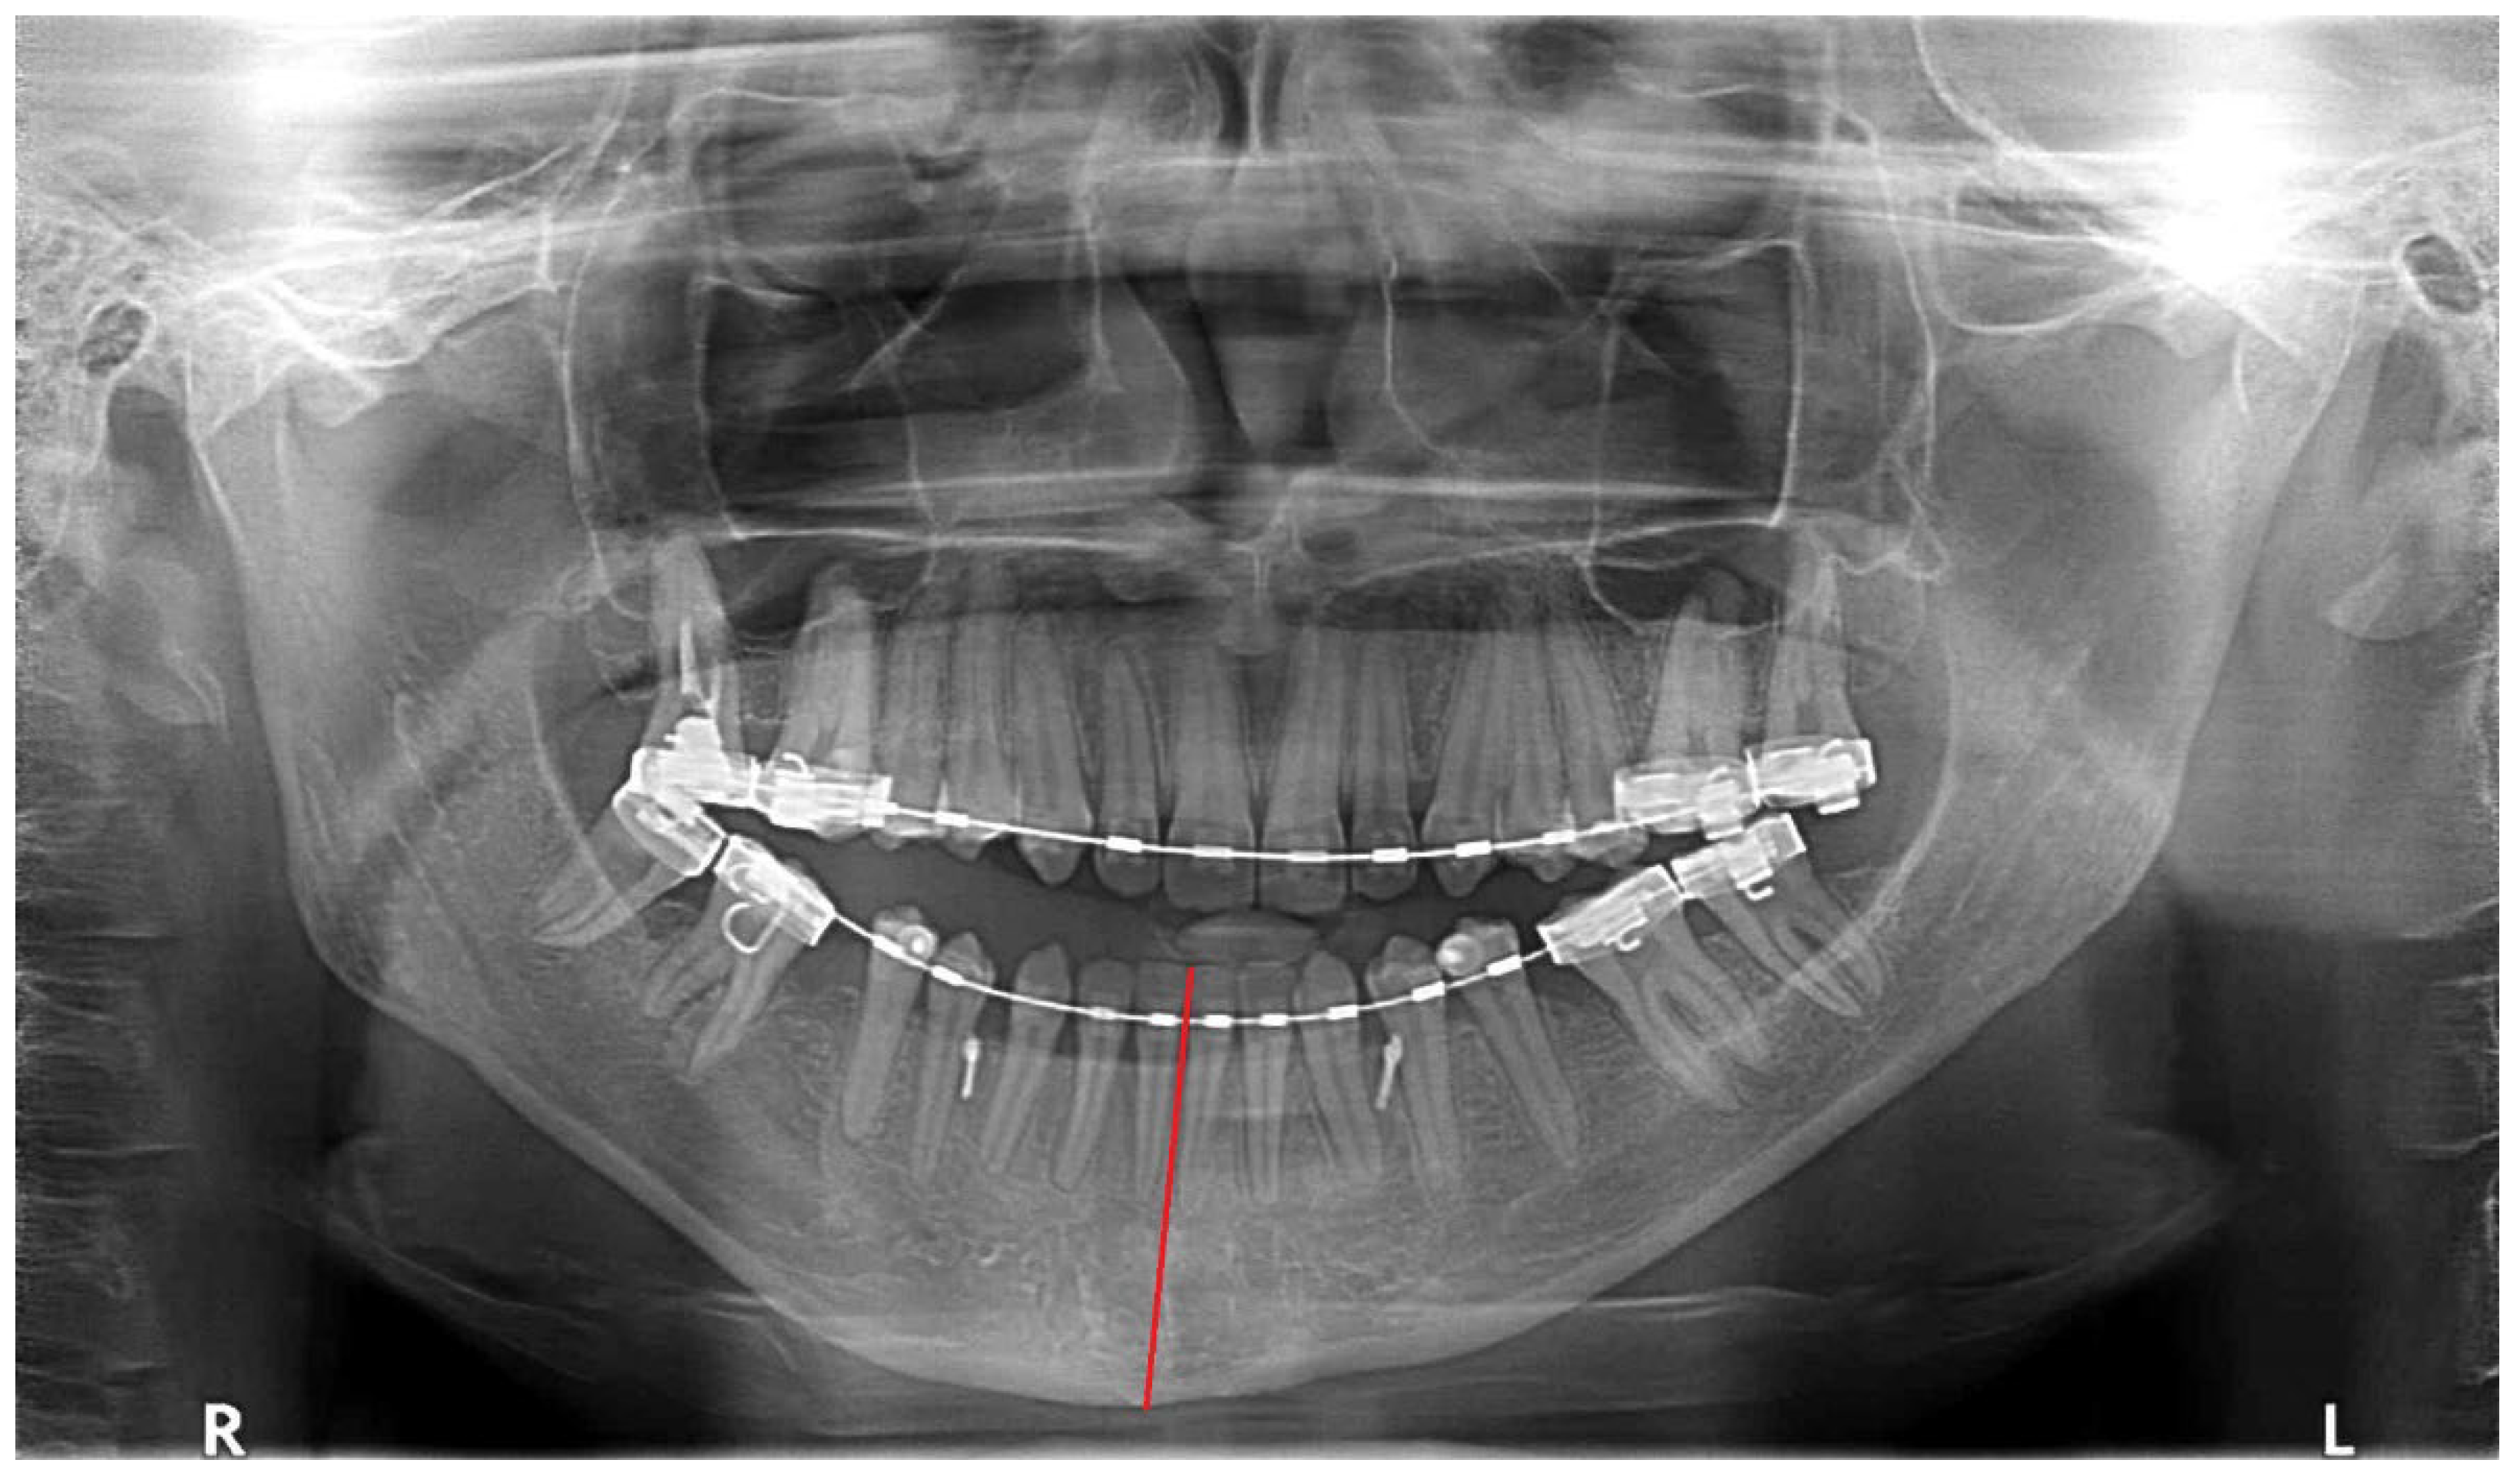

O—open bite at the canine, premolar area (Figure 2)—visible in RTG as the enlarged distance from upper and lower dentition on the HH side;-greatly related to individual factors especially the degree and occurrence time of pathological growth;

Figure 2. Visible open bite and increased vertical distance between upper and lower anterior teeth.